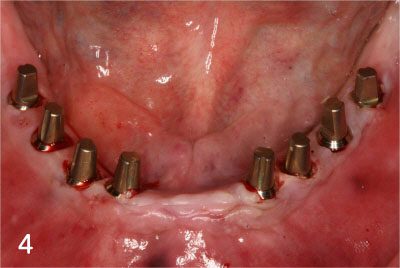

5. Immediate Loading after implant placement

Totally edentulous status on lower jaw

Fit surgical guide for precise implant placement

Removal of gum at exact site for implant placement with dental laser

Placing Implants

Connection of temporary cylinder for provisional bridge

Provisional bridge to use right after placing implants

This is after bonding provisional bridge. Patient can have strong teeth in a few hours